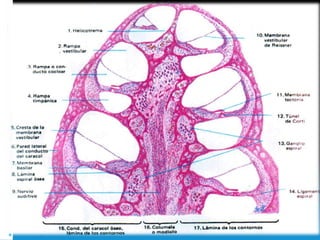

Sentido del Oído

Oído Interno

Laberinto membranoso Laberinto óseo

 Conducto coclear

 Sáculo

 Utrículo

 Conductos semicirculares

 Saco y conducto

endolinfatico

 Vestíbulo

 Conducto semicircular

Periostio

 Perilinfa

Sonido y Corti

Conducto coclear

2 ¾ giro

Divertículo tubular

fondo ciego

Vestibular timpánica-

perilinfa

C:Coclear- endolinfa